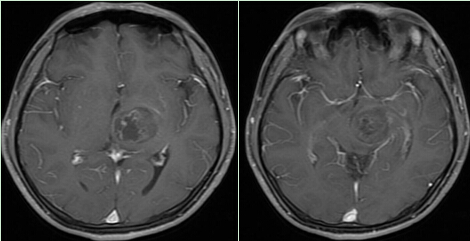

图4 术后MRI示肿瘤全切除